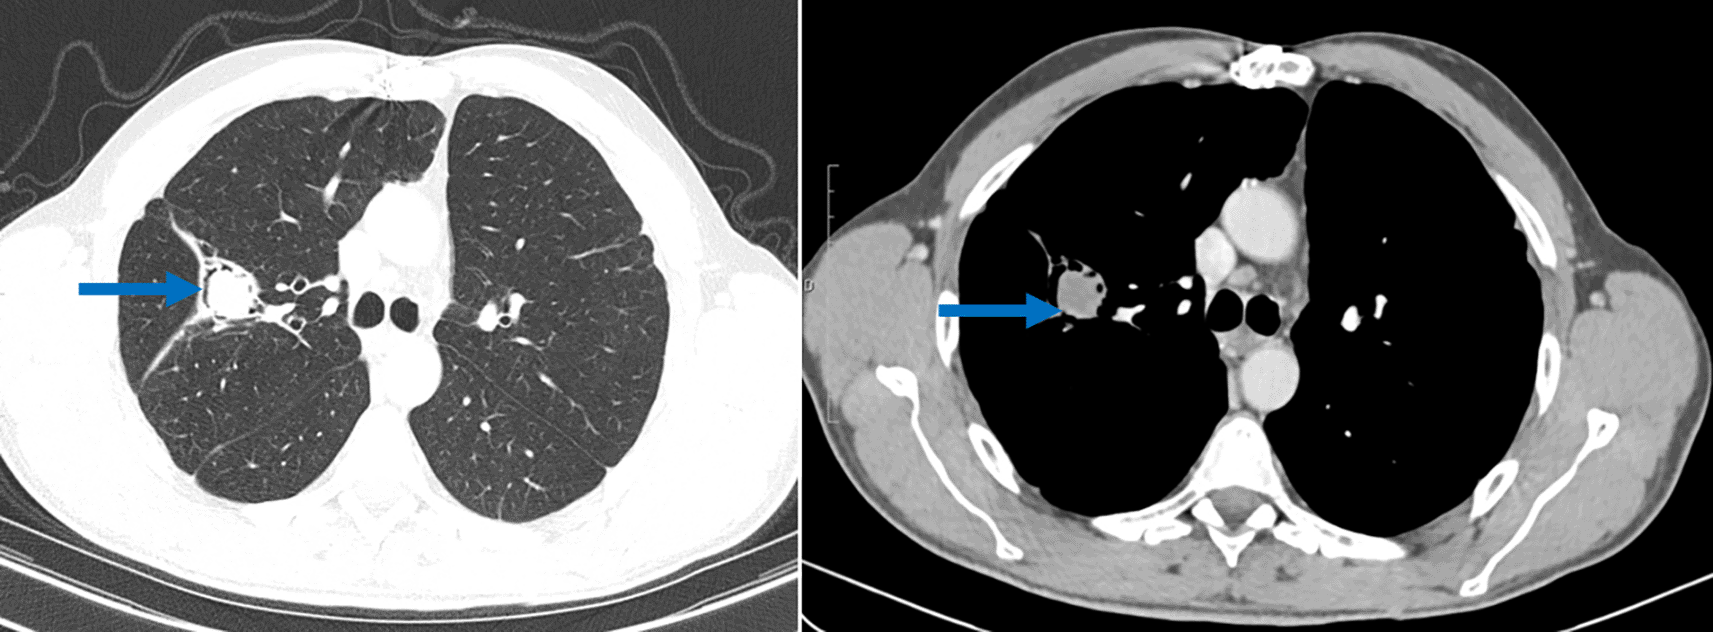

During regular post-surgical follow-up, 5 years post the last surgery, a scannographic imaging revealed fluid-density endo-bronchial material in the right superior lobe (lung cavity sequelary to the previous cystectomy) separated from the cavity wall by airspace (“air crescent” sign). This image was typical of pulmonary aspergilloma (Figure 3). Although the Aspergillus serology showed doubtful results, the clinical context together with the CT scan findings were highly suggestive of a pulmonary aspergilloma. Blood tests showed high levels of IgE. A surgical resection of the cavity was scheduled but not yet performed.

Another intriguing finding in this case report was the discovery of an aspergilloma, on the lung cavity. Pulmonary aspergilloma occurs as a colonizer of pre-existing pulmonary cavity of any etiology such as tuberculosis sequelae, cavitary neoplasia or operated hydatid cyst and it is a saprophytic infection.11 Aspergilloma has rarely been described in operated hydatid cyst cavities in immunocompetent patients.12 For this patient, the aspergilloma was discovered two years after the lung surgery. A very similar case of a 56-year-old patient, who presented with an aspergilloma of the upper right lobe following cystectomy, have been reported by M. El Hammoumi et al.12